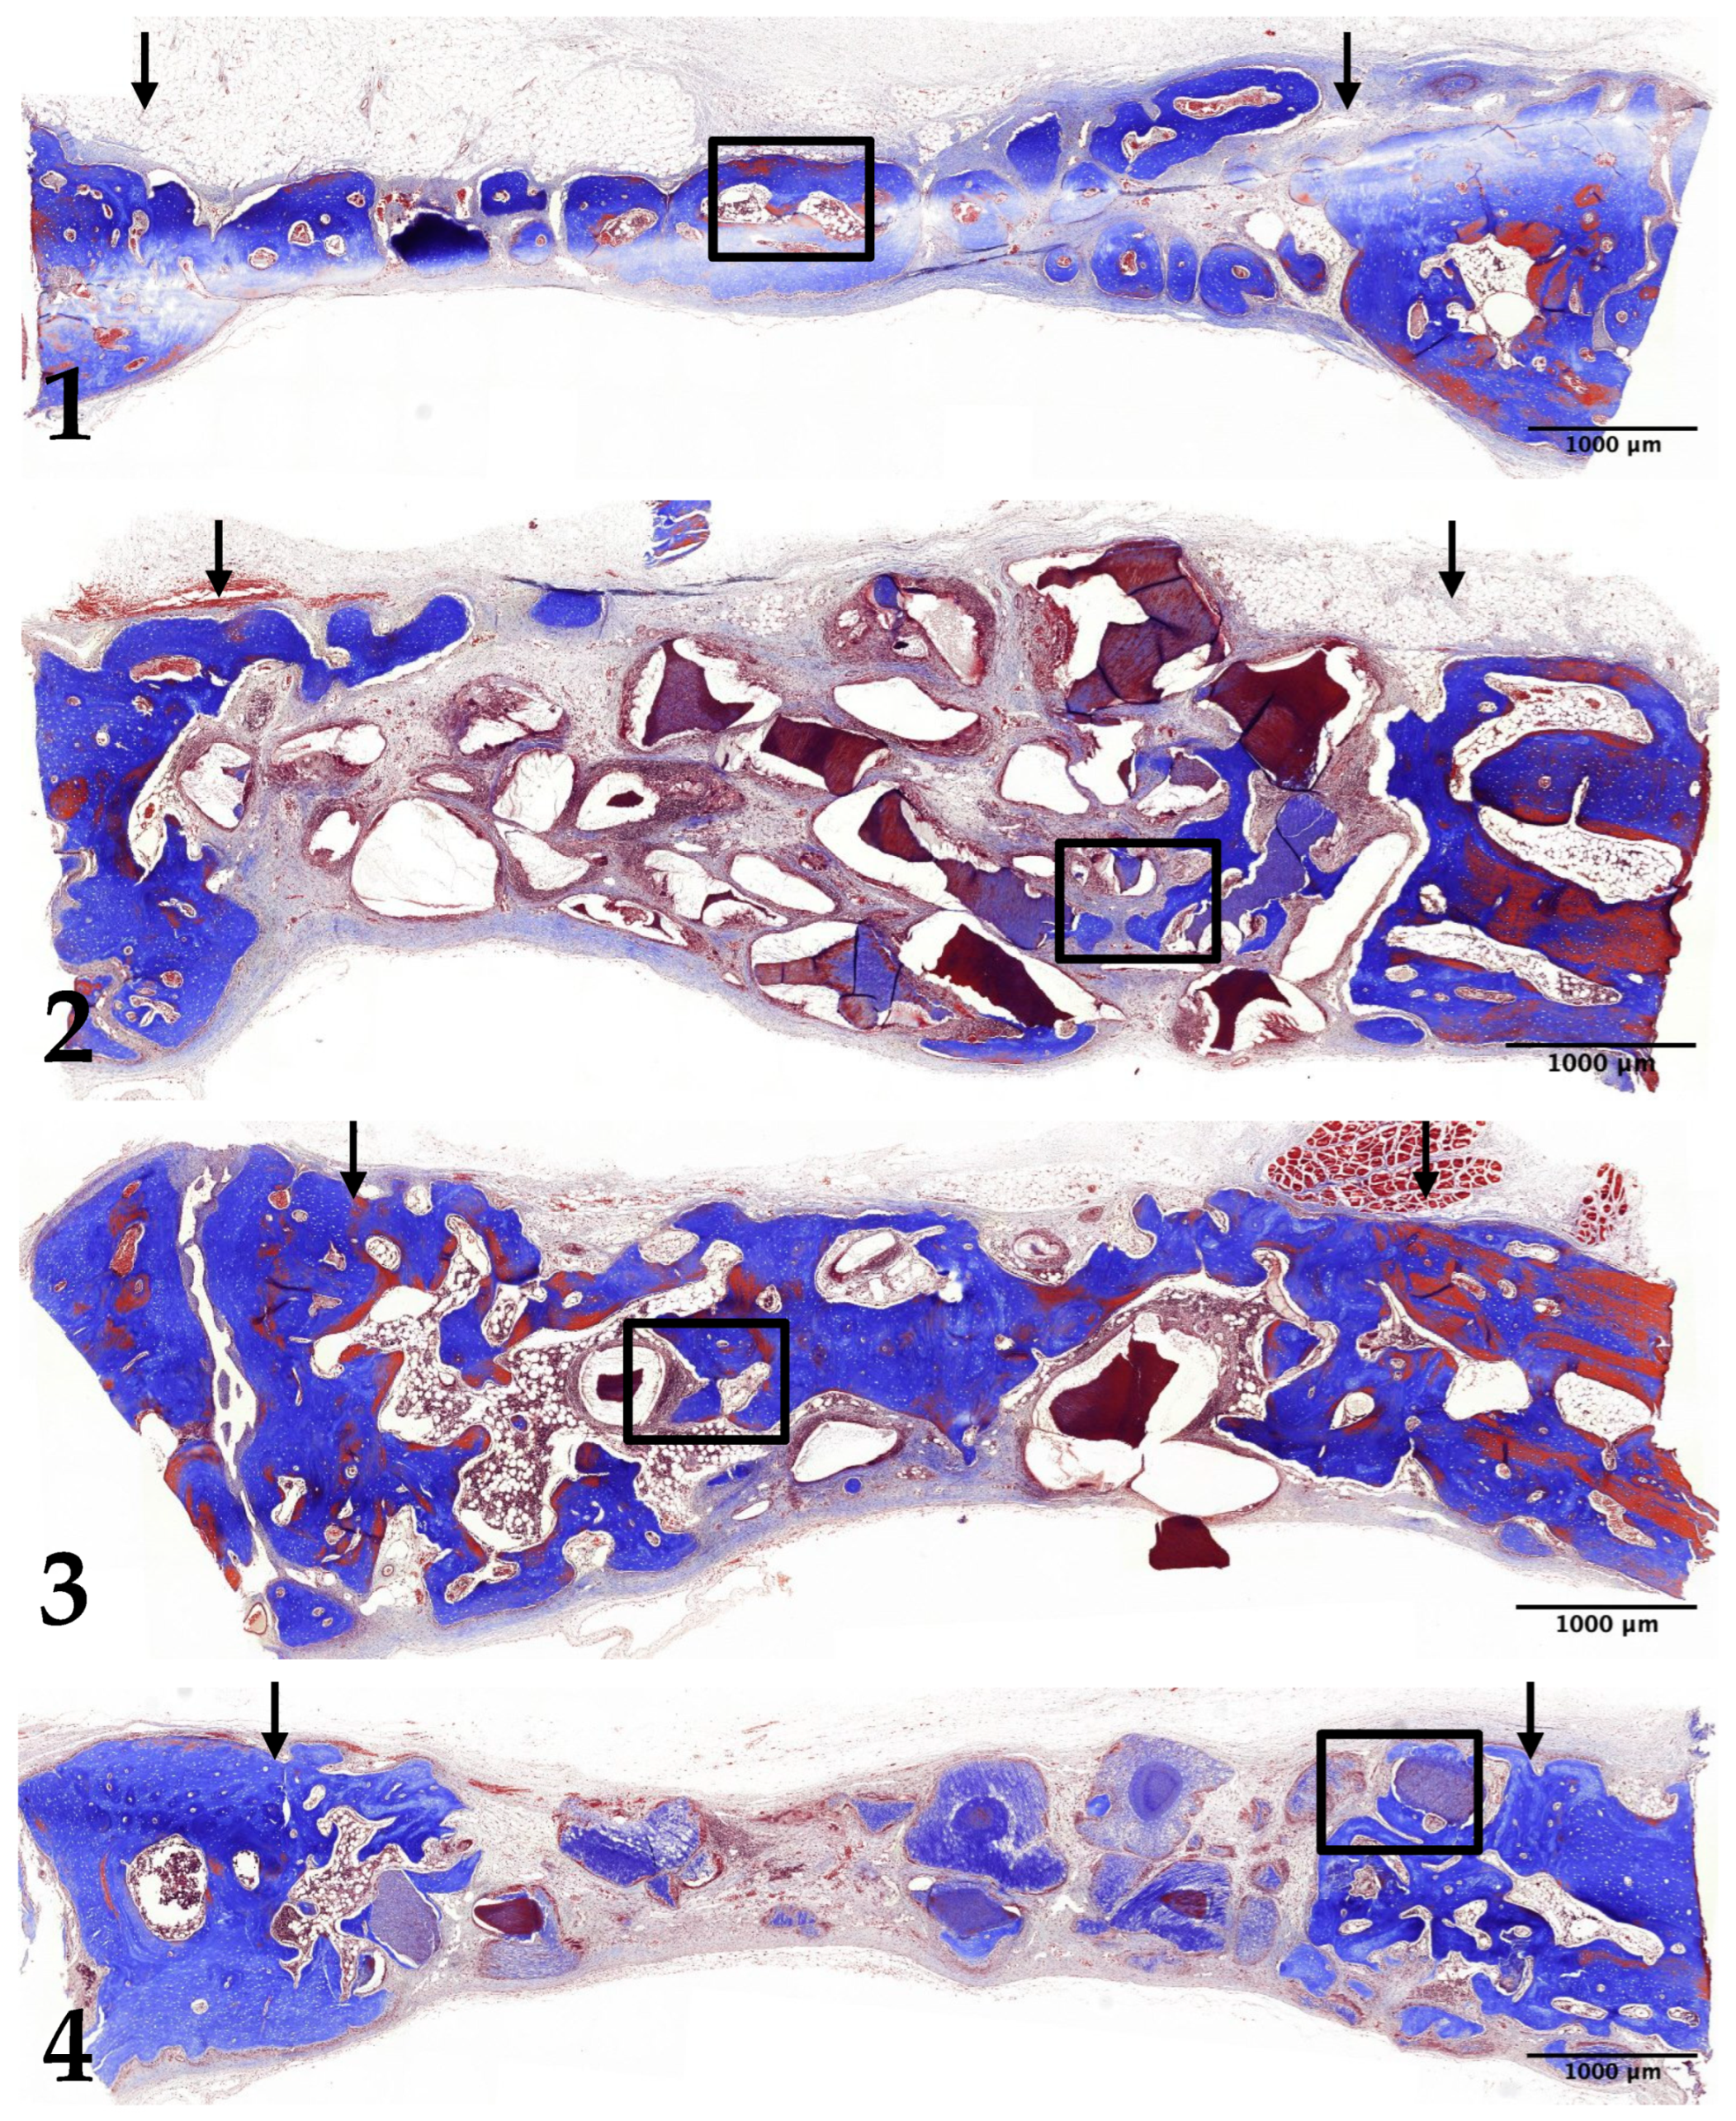

3.1. Histological Analysis

3.2. Two-Week Results

3.3. Four-Week Results

3.4. Eight-Week Results